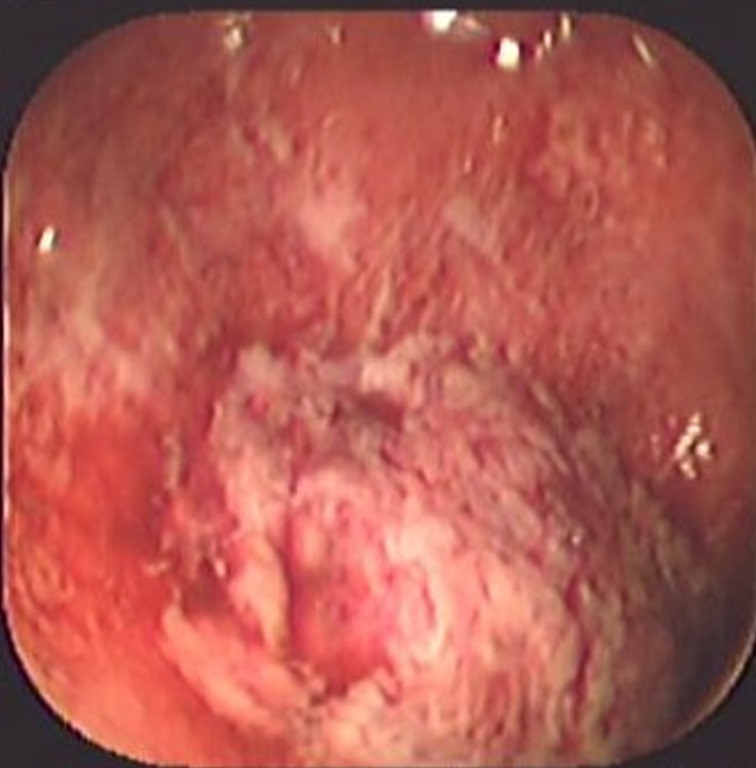

Colitis ulcerosa crónica inespecífica

Envíado por Dr. Carlos Ernesto Arévalo